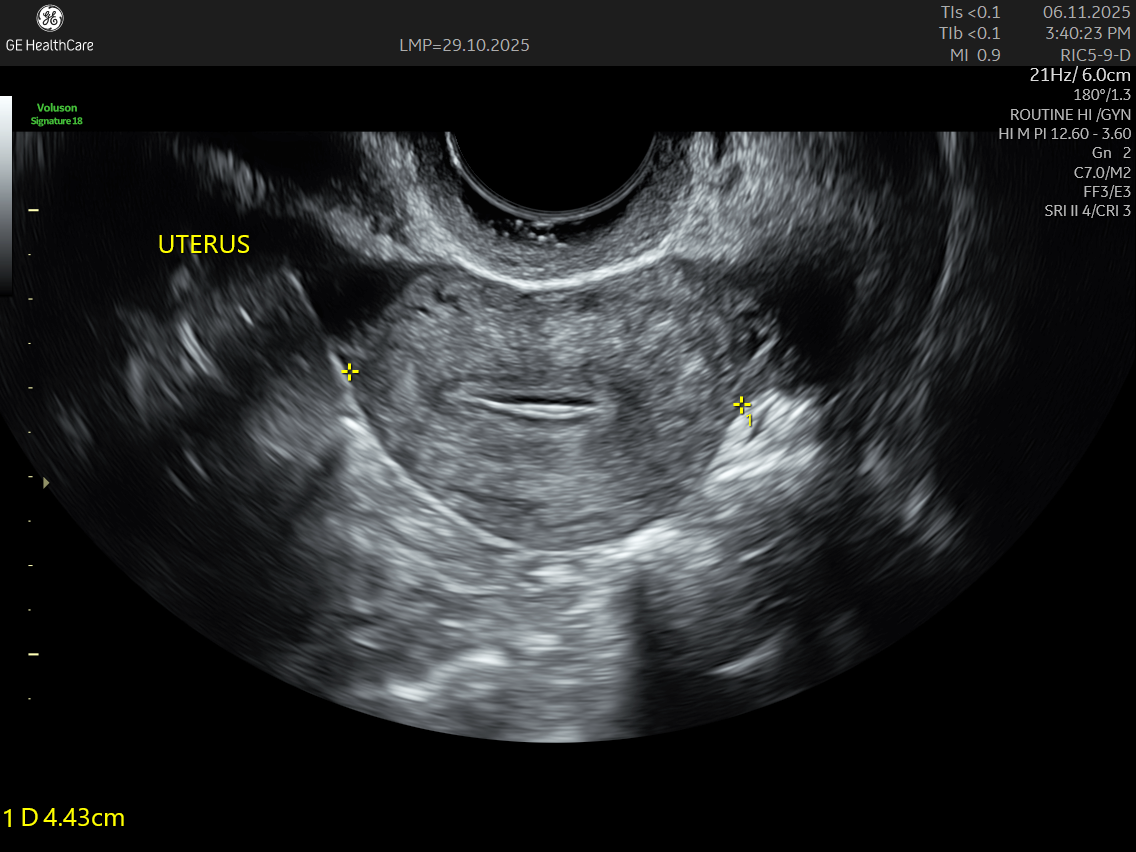

IMAGE GALLERY